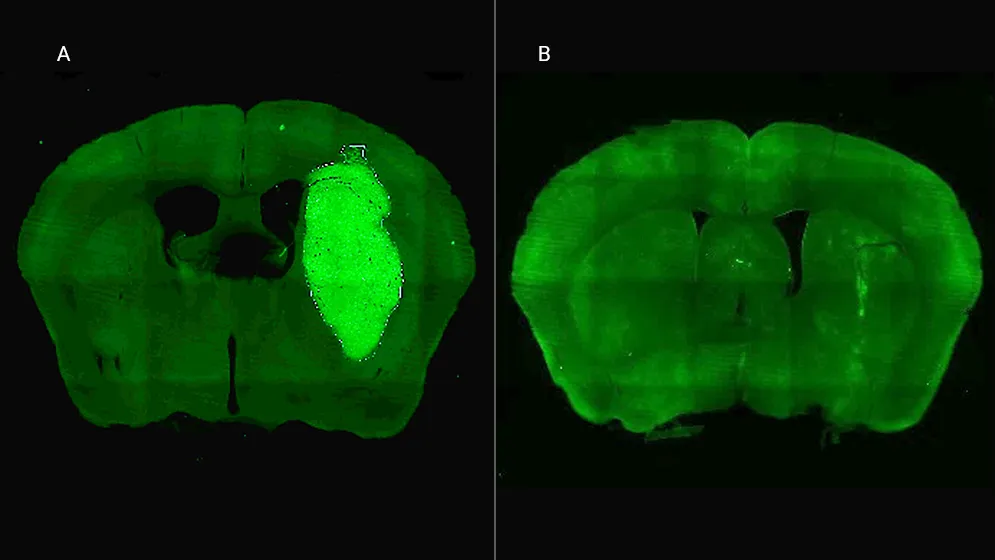

En estudios in vivo, el equipo liderado por Candolfi utilizó ratones inoculados en el cerebro con neuroesferas que contienen lesiones características de los tumores humanos que fueron desarrollados por el laboratorio de la científica argentina y colaboradora del estudio María Castro en la Universidad de Michigan, en Estados Unidos. Para tratar los tumores in vivo, los equipos de Candolfi y de la también científica del CONICET Flavia Zanetti, del Instituto de Ciencia y Tecnología César Milstein (CONICET- Fundación Pablo Cassará), desarrollaron un vector adenoviral que expresa la molécula o péptido P60 al interior de las células tumorales.

“Esta estrategia permite la expresión sostenida de P60 en la zona del tumor, facilitando la terapia y reduciendo la probabilidad de efectos colaterales sistémicos. Una inyección intratumoral del vector inhibió el crecimiento del tumor y mejoró notablemente la respuesta a la quimioterapia, llevando a la erradicación del tumor y sobrevida a largo plazo en un tercio de los ratones con tratamiento combinado”, afirma Candolfi. Y agrega: “No observamos efectos neurotóxicos con ninguno de los tratamientos empleados, por lo tanto, esta estrategia tendría buen perfil de seguridad para tratar estos tumores”.